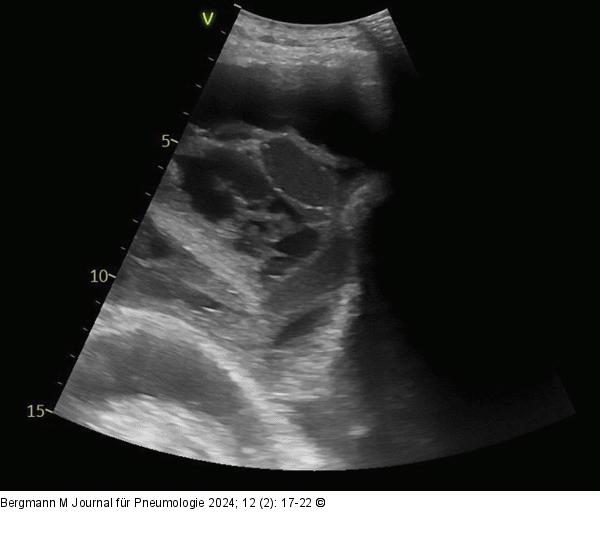

Abbildung 2: Septierter Erguss Septierter Erguss im Ultraschall |